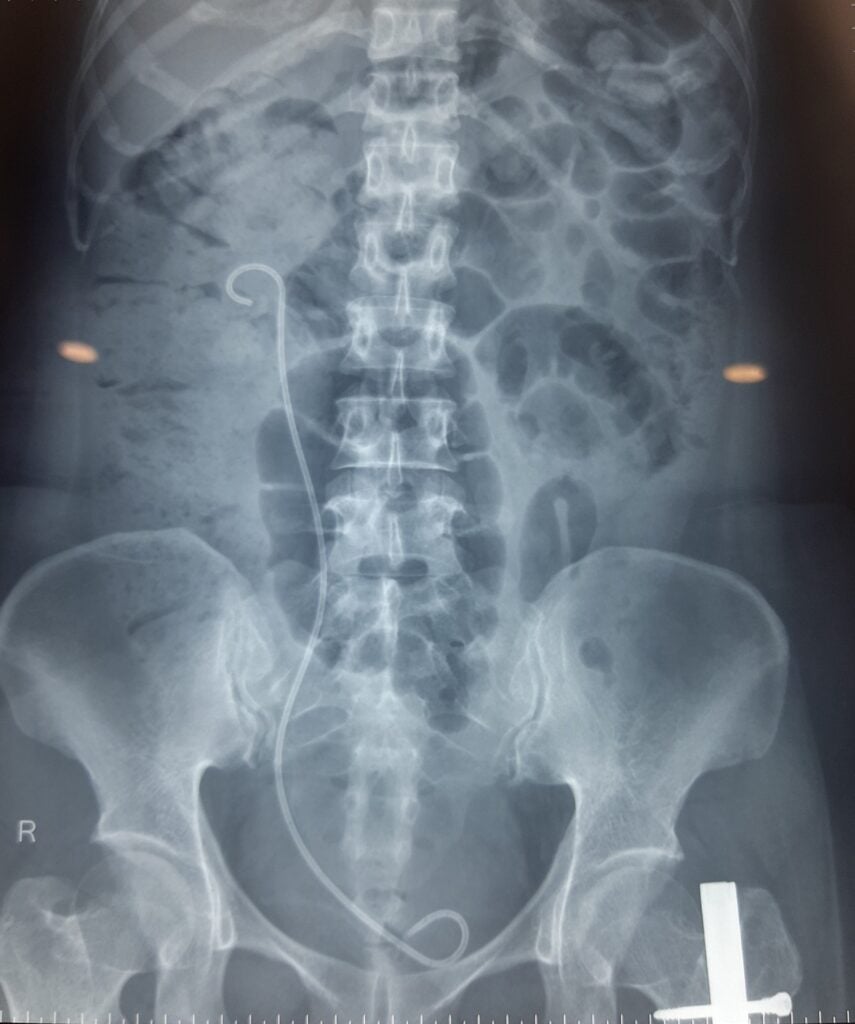

Trong vòng 3 giờ đồng hồ, đội ngũ y bác sĩ của bệnh viện với nhiều kinh nghiệm trong xử trí các trường hợp sỏi phức tạp đã thực hiện thành công ca phẫu thuật, loại bỏ sỏi khỏi đường tiết niệu cũng như đặt sonde JJ mới. Sau phẫu thuật, tình trạng sức khỏe của chị T. ổn định, diễn tiến tốt và đã được xuất viện sau 5 ngày điều trị. Chụp phim X quang kiểm tra sau mổ cho thấy chị T. đã hết sỏi trong thận.

Hình ảnh X quang kiểm tra sau phẫu thuật, sỏi đường tiết niệu đã được loại bỏ hoàn toàn, sonde JJ mới được đặt cho người bệnh